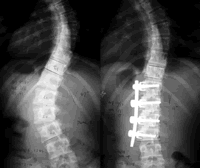

AIS的治疗方案包括非手术治疗和手术治疗,一般将侧凸的冠状面Cobb角是否超过40°作为是否选择手术治疗的决策依据。

临床上通常根据冠状面的Cobb角、骨骼发育情况、脊柱矢状面变化、椎体旋转程度及侧凸的自然病史判断是否需手术治疗。一般认为,对处于生长期、Cobb角>40°、非手术治疗无效(6个月内侧凸进展超过5°)、伴有疼痛、胸椎前凸及伴明显外观畸形的患者应选择手术治疗 ......